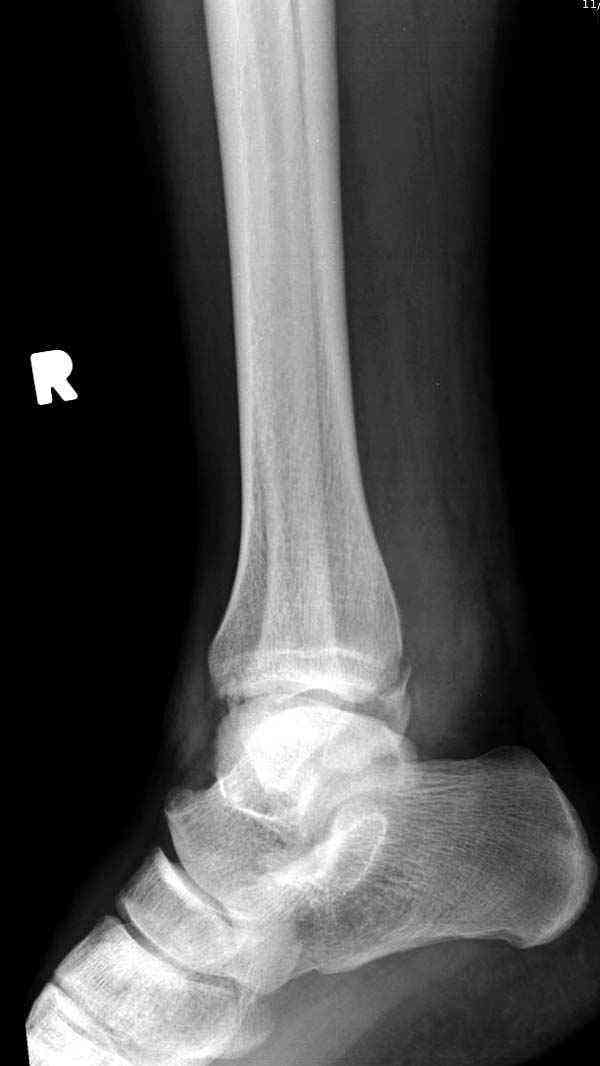

Нет первичных снимков, перелом очень низкий и под большим сомнением диагноз разрыва синдесмоза. Медиальная сторона отрепонирована на "хорошо" и, по-видимому, прорезание проволоки произошло во время операции. Без снимков трудно судить о высоте малоберцовой, а лодыжка находится в варусе. Лагирование получилось, но возле тонких шурупов передне-задний шуруп выглядит немного тяжеловато.

Коллеги правы, что при рутинных переломах достаточным бывает обычные снимки с мортизом. А стрессовые рентгенограммы могут уточнить, есть ли разрыв синдесмоза.

Здесь несколько частных случаев: перелом голеностопа со сравнительными снимками и разрыв синдесмоза, а также медиальная Hook пластина.